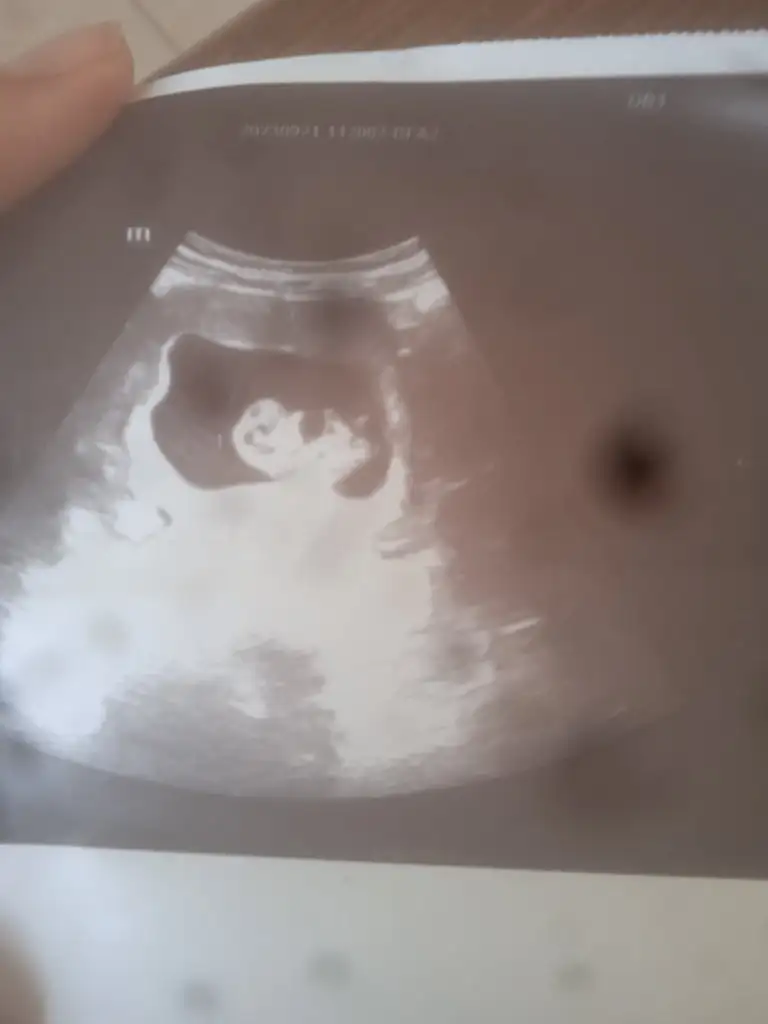

Merhaba ben de tahmin alabilir miyim? Tesekkurler:)

Eklentiler

• InCollage_20231118_134950662.webp

InCollage_20231118_134950662.webp

55,1 KB · Görüntüleme: 75

Arkadaşlar merhaba daha önce burada ultrason fotoğrafına bakıp cinsiyet tahmin edenleri görmüştüm benim içinde bi heyecan olur:) var mıdır tahmininiz normalde 12+4 üm ama ultrasonda 13 haftalık görünüyor